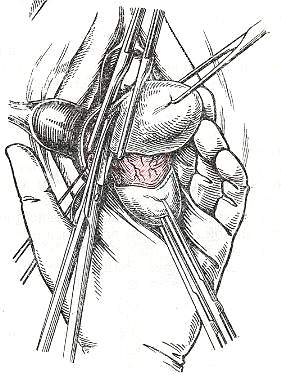

Современные методы лапаротомии и миомэктомии